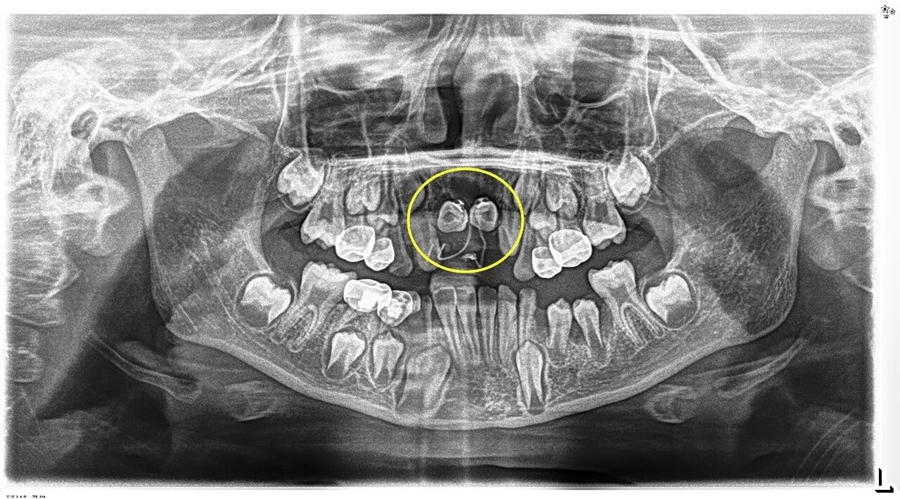

埋伏牙一旦发现,应及早处理。针对小胡的情况,口腔团队在完成多生牙的拔除后,为埋伏牙粘接牵引装置,通过温和的正畸力对受影响的恒中切牙进行“牵引导萌”,"拉" 回正常生长轨道。

术后小胡恢复非常顺利。第一次复查时,两颗恒中切牙的舌侧扣和弹性附件的影像,下图可见: